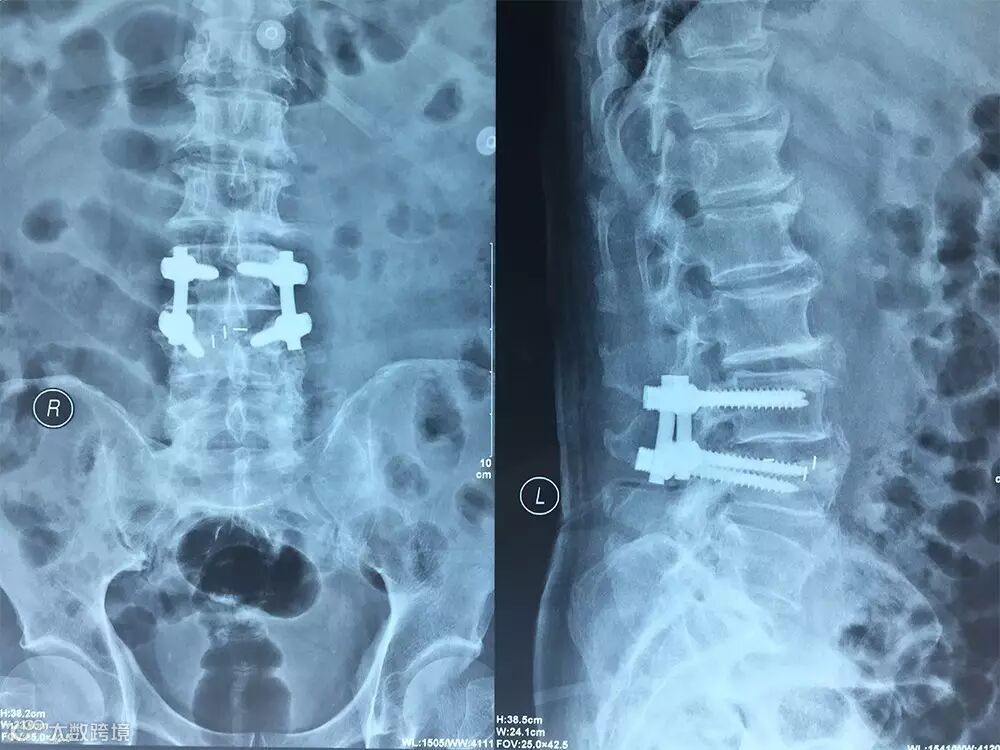

【术前X线】